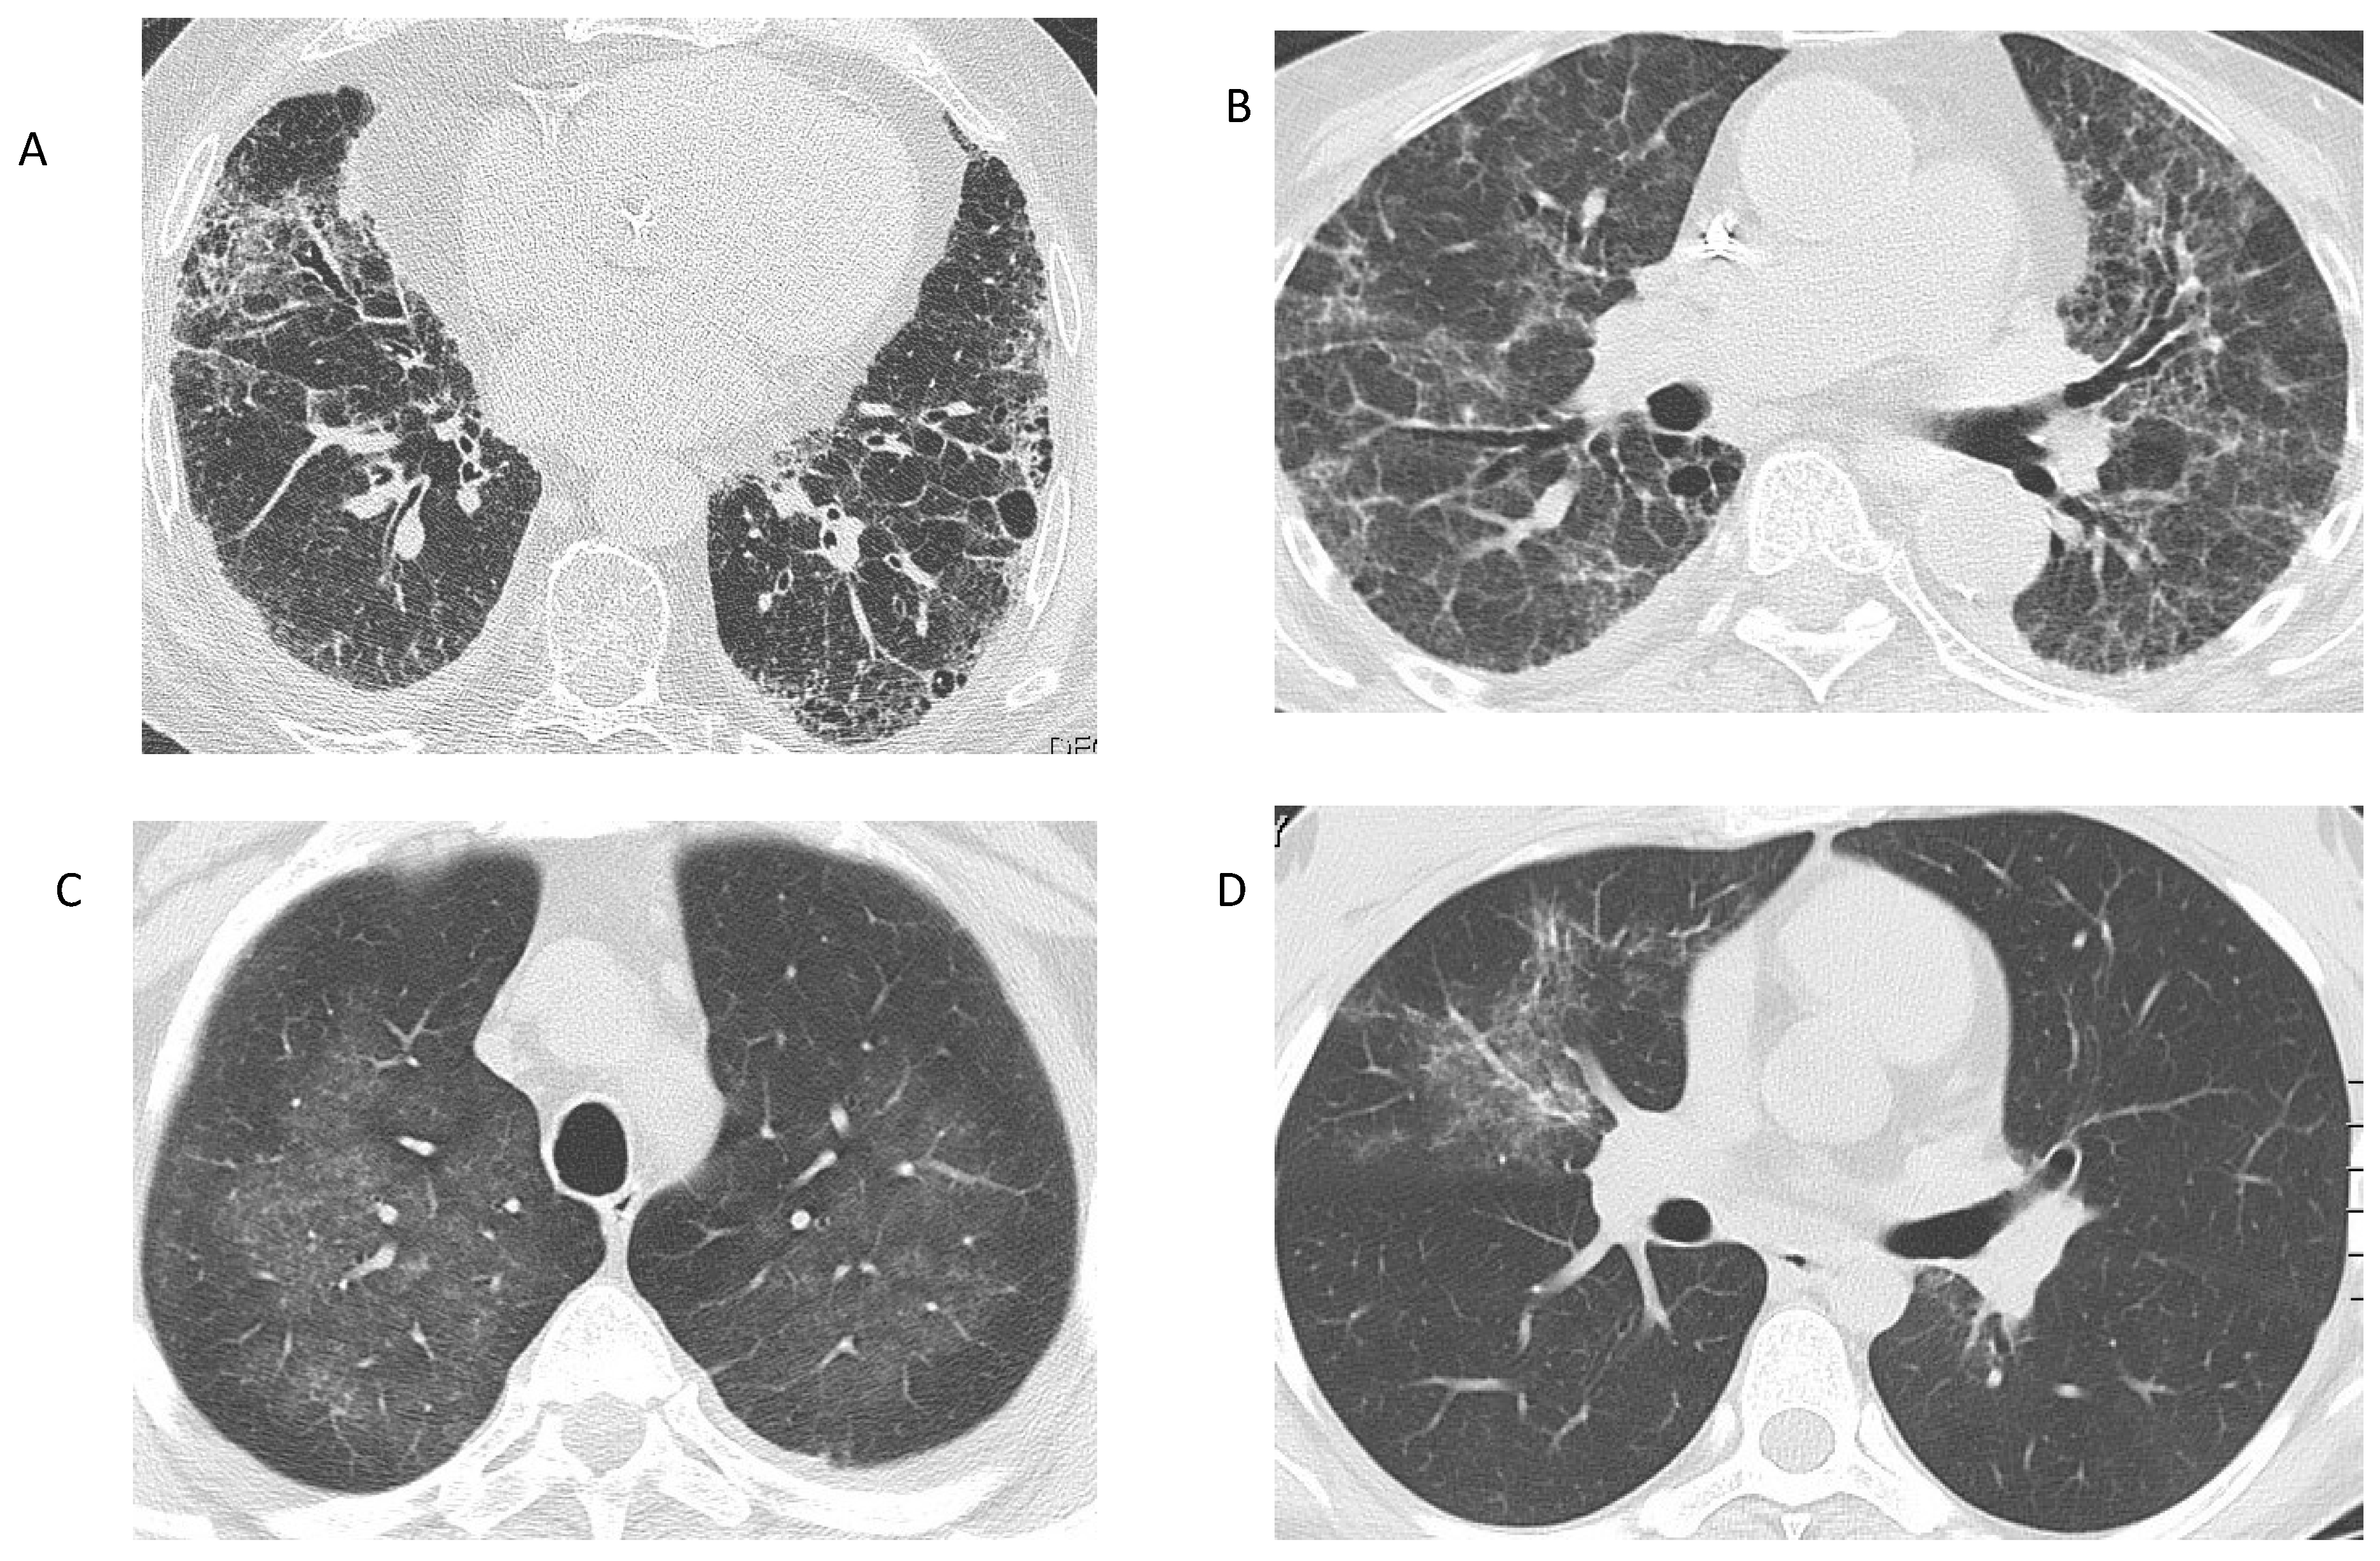

2.1. GPA and MPA

- Sacoto, G.; Boukhlal, S.; Specks, U.; Flores-Suárez, L.F.; Cornec, D. Lung involvement in ANCA-associated vasculitis. Presse Med. 2020, 49, 104039. [Google Scholar] [CrossRef]